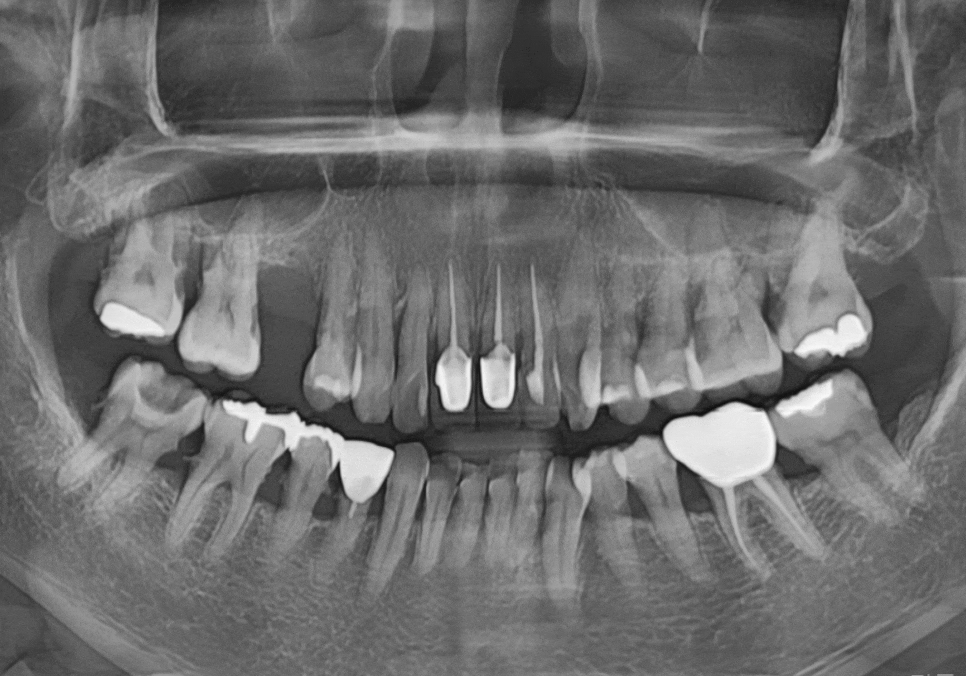

방사선 사진을 살펴볼게요~

매끈해보여야 할 치아 뿌리 쪽에

돌기처럼 무언가 붙어있는게 보이시나요?

바로 치석인데요.

사실 치석은 밀도가 낮아

방사선 사진상에는

잘 나타나지 않는 경우가 많아요.

그런데 만약 엑스레이 사진에서

이처럼 치아 옆면이 매끄럽지 않고

돌기처럼 튀어나온 것이 보인다면,

그건 치석이 이미 엄청나게

두껍고 단단하게 쌓였다는 뜻이에요..ㅜㅜ

#47 치아: 수직 파절(완전히 쪼개짐)

#47,46,45, #31,32,33, #16,14 : 치아흔들림

전체적인 상태: 잇몸뼈가 녹아

치조골 수평이 매우 낮아진 상태